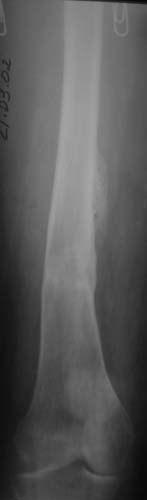

с удлинением правой ноги за счет бедра на уровне диафиза. В последнее время прогрессируют боли в правом тазобедренном суставе, порочное положение правой ноги, затруднена ходьба.Вопросы:1) Целесообразно ли эндопротезирование правого тазобедренного сустава?2) Целесообразный ли следующие действия: канал бедренной кости предполагаем вскрыть для введения ножки протеза на высоте угловой деформации, предполагаем низведение большого вертела с мышцами; протез будет подобран индивидуально, предполагается умеренная версия?В приложении рентгенограммы и трехмерная КТ.В цветном и более качественном варианте КТ размещена здесь

2. К сожалению, техника операции, представленная коллегами из Москвы здесь не получится, т.к. остеотомия бедренной кости была выполнена достаточно низко (по отношению к области сустава). На мой взгляд, целесообразно выполнить остеотомию на высоте деформации с основанием клина кнутри (что бы не было дефекта кости)и ввести понопокрытую ножку с проксимальной и дистальной фиксацией (по типу AML, ее длина 180 мм, при необходимости можно и 200 мм, надо рассчитать). Стабильность ножки будет обеспечена дистальной ее фиксацией, если будут сомнения относительно прочности фиксации короткого проксимального фрагмента, то линию остеотомии можно перекрыть кортикальными аллографтами.